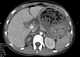

Fluid-filled stomach

Duodenal atresia is the congenital absence or complete closure of a portion of the lumen of the duodenum. It causes increased levels of amniotic fluid during pregnancy (polyhydramnios) and intestinal obstruction in newborn babies. [Source: Wikipedia ]